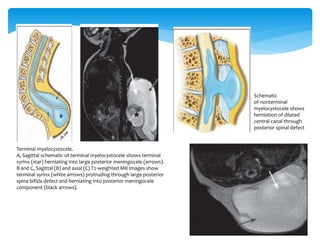

Terminal myelocystocele.

A, Sagittal schematic of terminal myelocystocele shows terminal

syrinx (star) herniating into large posterior meningocele (arrows).

B and C, Sagittal (B) and axial (C) T2-weighted MR images show

terminal syrinx (white arrows) protruding through large posterior

spina bifida defect and herniating into posterior meningocele

component (black arrows).

Schematic

of nonterminal

myelocystocele shows

herniation of dilated

central canal through

posterior spinal defect